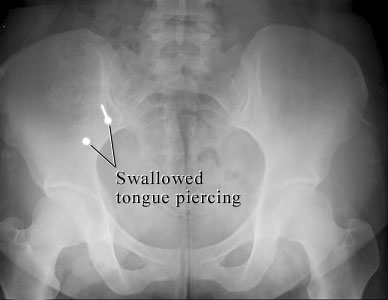

X-ray of swallowed mouth jewelry